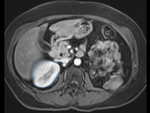

v3.6.3 This case is complete and up to date for version 3.6.3 Slicer Registration Library Case #17: Kidney pre-op MR to intra-op CT

fixed image/target: intra-operative CT moving image: per-operative MRI

CT, MRI, abdominal, image-guided therapy, IGT, tumor ablation

• fixed: intra-operative CT, oblique, 0.58 x 0.58 x 3 mm voxel size, dimensions 512 x 512 x 20

• moving: opre-operative MRI lique, 1.2 x 1.2 x 4 mm voxel size, dimensions 320 x 240 x 64

Registration Results

original unregistered original unregistered

after manual initial alignment after manual initial alignment

after rigid registration after rigid registration

after affine registration after affine registration